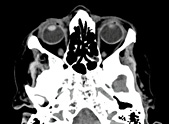

CT des Nervensystems (Neuroradiologie)

• Schädel

• Wirbelsäule

In der Neuroradiologie setzten wir die Computertomographie (CT) speziell ein zur Erstuntersuchung bei akuten Erkrankungen (Schlaganfall, Blutungen, Schädelverletzungen, Bandscheibenvorfall) und zur Nadelkontrolle bei der Entnahme von Gewebeproben (Biopsie).

Die CT-angiographische Darstellung der intrakraniellen Hirngefäße optimiert die sofortige Indikationsstellung zur Schlaganfall-Frühbehandlung mittels Lysetherapie. Diese bildgebende Methodik wird durch die Einführung der Perfusions-CT erheblich erweitert, das zusätzlich die Perfusionsverhältnisse in zirkulatorisch gestörten Hirnarealen aufzeigt.